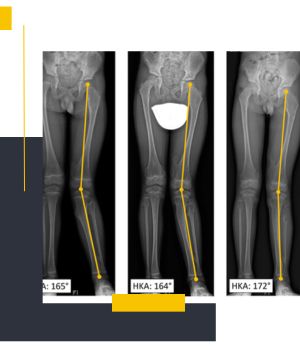

استفاده از دستگاههای دیجیتال نسل جدیدکیفیت بالای تصاویر و نمایش دقیق محور پا باعث میشود تشخیص و ارزیابی پزشکان با اطمینان بیشتری انجام شود.

تهیه عکس در حالت ایستاده برای بررسی واقعی محور اندام

عکسهای الایمنت ویو در مروارید ری طبق استانداردهای ارتوپدی و در وضعیت صحیح ایستاده گرفته میشود تا نتیجه کاملاً دقیق و قابل اعتماد باشد.